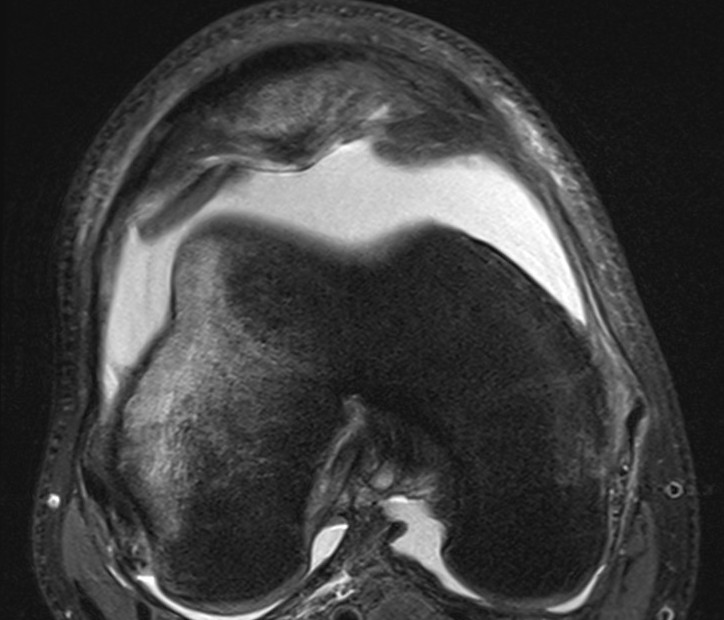

Large chondral fracture from medial facet of patella

Osteochondral fracture lateral femoral condyle